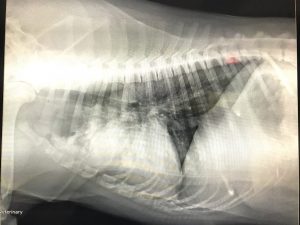

Sometimes, in the course of care, your pet may need to stay with us for a short time to ensure a full recovery. This may be necessary following extensive surgery, injury, or illness. Black Creek Veterinary Hospital has the ability to fully care for your pet’s every need, with complete intensive care services in addition to multimodal post-op and recovery treatments.

Whether your pet needs intensive care to ensure recovery from a severe injury, basic monitoring after surgery, or something in between, our caring veterinarians and staff will be there to provide all the attention your pet needs to get well again.

At any time when consistent daytime monitoring or attention to an illness is required, we use state of the art equipment to keep tabs each patient’s pulse, temperature, and vitals. Oxygen therapy is also available to pets facing with respiratory complications. All monitoring and intensive care is provided alongside constant supervision. Any necessary medications will also be readily available from our compassionate technicians.